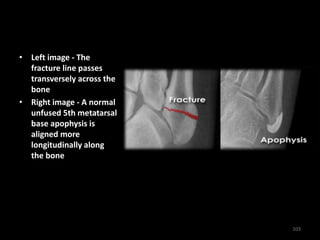

5th metatarsal base

• Left image - The

fracture line passes

transversely across the

bone

• Right image - A normal

unfused 5th metatarsal

base apophysis is

aligned more

longitudinally along

the bone